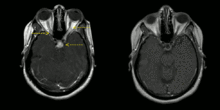

Right image: MRI brain with contrast showing near resolution of enhancement after treatment.

The diagnosis of neurosarcoidosis often is difficult. Definitive diagnosis can only be made by biopsy (surgically removing a tissue sample). Because of the risks associated with brain biopsies, they are avoided as much as possible. Other investigations that may be performed in any of the symptoms mentioned above are computed tomography (CT) or magnetic resonance imaging (MRI) of the brain, lumbar puncture, electroencephalography (EEG) and evoked potential (EP) studies. If the diagnosis of sarcoidosis is suspected, typical X-ray or CT appearances of the chest may make the diagnosis more likely; elevations in angiotensin-converting enzyme and calcium in the blood, too, make sarcoidosis more likely. In the past, the Kveim test was used to diagnose sarcoidosis. This now obsolete test had a high (85%) sensitivity, but required spleen tissue of a known sarcoidosis patient, an extract of which was injected into the skin of a suspected case.[1]

MRI with gadolinium enhancement is the most useful neuroimaging test. This may show enhancement of the pia mater or white matter lesions that may resemble the lesions seen in multiple sclerosis.[1]